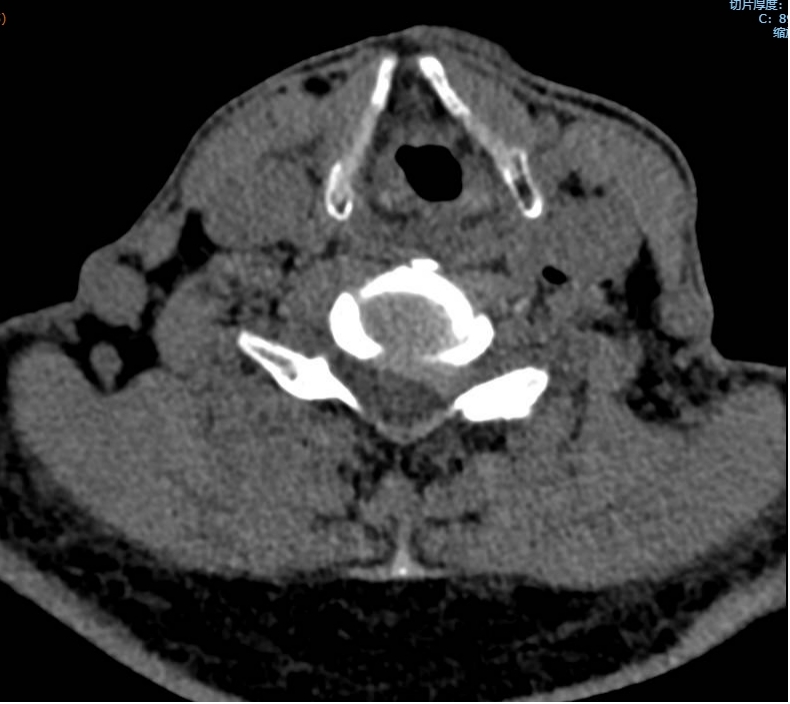

黃大伯今年70歲,入院前10多天出現(xiàn)左側(cè)肩背部疼痛及左上肢疼痛、麻木,患病以來根本不能平臥,就連睡覺也只能一直坐著,在院外治療后病情無緩解,反而加重,怎么回事呢?輾轉(zhuǎn)來到瀘州市中醫(yī)醫(yī)院疼痛科治療。由于疼痛嚴(yán)重,外加嚴(yán)重缺乏睡眠,黃大伯入院時焦慮、精神狀態(tài)很差??粗鼻邢虢獬纯嗟难凵?,疼痛科醫(yī)生團...